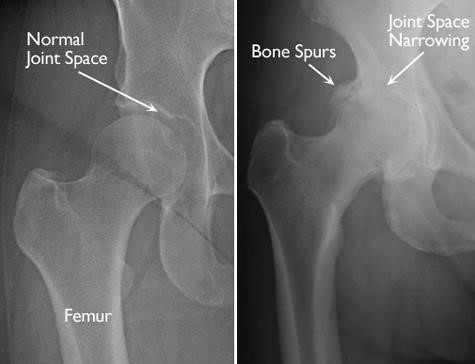

In osteoarthritis, the cartilage in the hip joint becomes damaged and gradually wears away over time. As the cartilage wears away, it becomes frayed and rough, and the protective joint space between the bones decreases. This can result in bone rubbing on bone. To make up for the lost cartilage, the damaged bones may start to grow outward and form bone spurs (osteophytes).

(Left) In this x-ray of a normal hip, the space between the ball and socket indicates healthy cartilage. (Right) This x-ray of an arthritic hip shows severe loss of joint space and bone spurs.